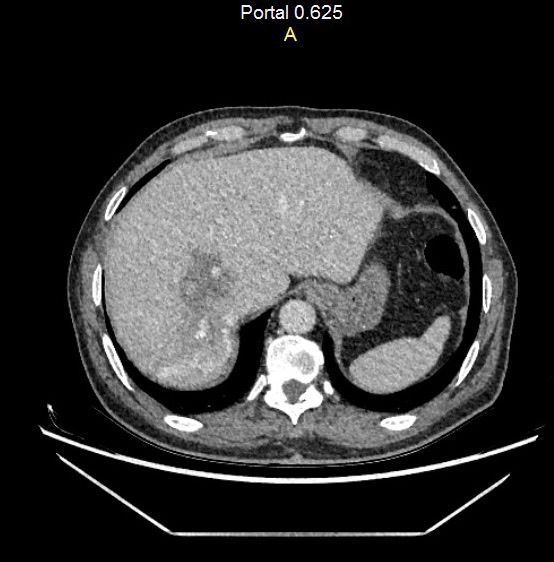

A 62 yeas old man presented to the hospital with liver metastatic tumor due to the primer tumor in the sigmoid colon. The patient has had an intermittent epigastric pain for 4-5 years. Both the liver and the tumor in the sigmoid colon are inoperable at the same time. Therefore, the doctors gave a decision to an operation called “right extended hepatectomy”, where segment 8,7,6,5,4 will be dissected. 2 months later the sigmoid colon will be observed for an operation as planned.